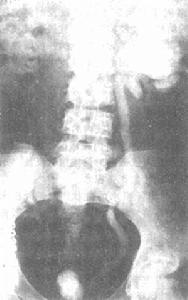

3.膀胱造影:膀胱容量明顯縮小,呈圓形,邊緣光滑。多出現輸尿管返流及腎積水。